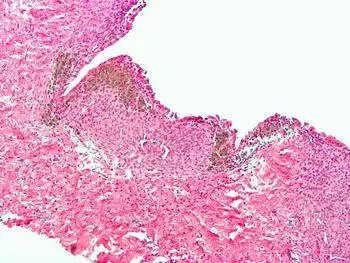

Histopathology

For a histopathological diagnosis, at least two of the following three criteria should be present:[101]

Immunohistochemistry has been found to be useful in diagnosing endometriosis as stromal cells have a peculiar surface antigen, CD10, thus allowing the pathologist go straight to a staining area and hence confirm the presence of stromal cells and sometimes glandular tissue is thus identified that was missed on routine H&E staining.[102]